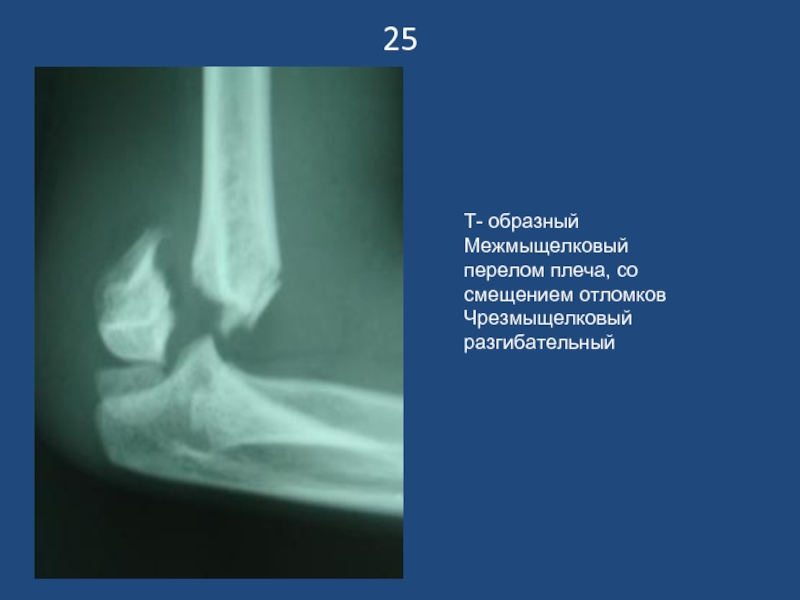

Слайд 2625

Т- образный Межмыщелковый перелом плеча, со смещением отломков

Чрезмыщелковый разгибательный